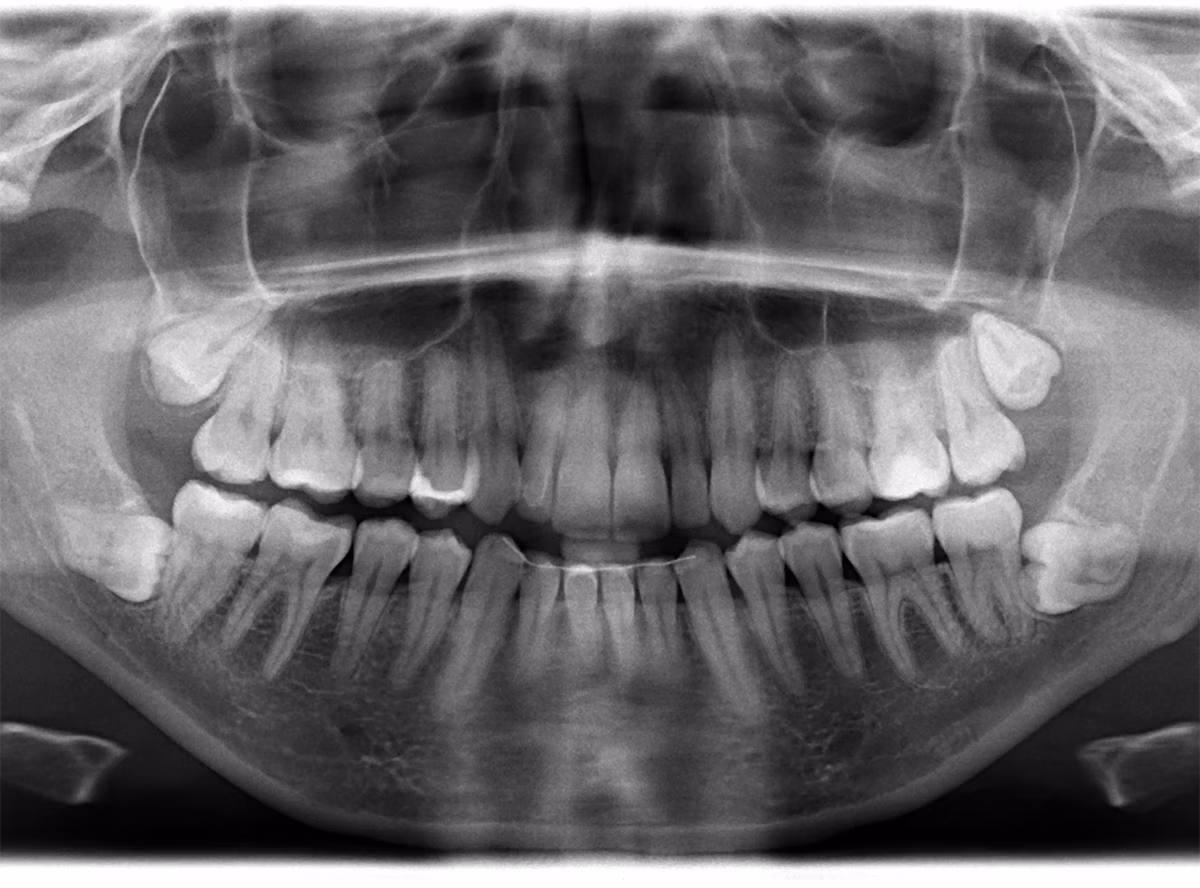

Wisdom teeth, or third molars, often emerge in your late teens or early twenties and can cause pain, crowding, or infection if they don’t have enough room to grow properly. Our experienced team provides the best wisdom teeth removal in Leander, ensuring safe, efficient, and comfortable extraction, whether your wisdom teeth are erupted, partially impacted, or fully impacted. We use modern imaging and surgical technology to ensure predictable, comfortable results and faster healing.

Your dentist will perform a comprehensive oral exam, take digital X-rays, and discuss sedation and anesthesia options to ensure a comfortable, pain-free experience.

For simple extractions, the tooth is gently loosened and removed with specialized instruments. For surgical extractions or impacted wisdom teeth, small incisions may be made to remove the tooth with minimal disruption to the surrounding tissue, safely. Our modern approach ensures accuracy and faster healing.